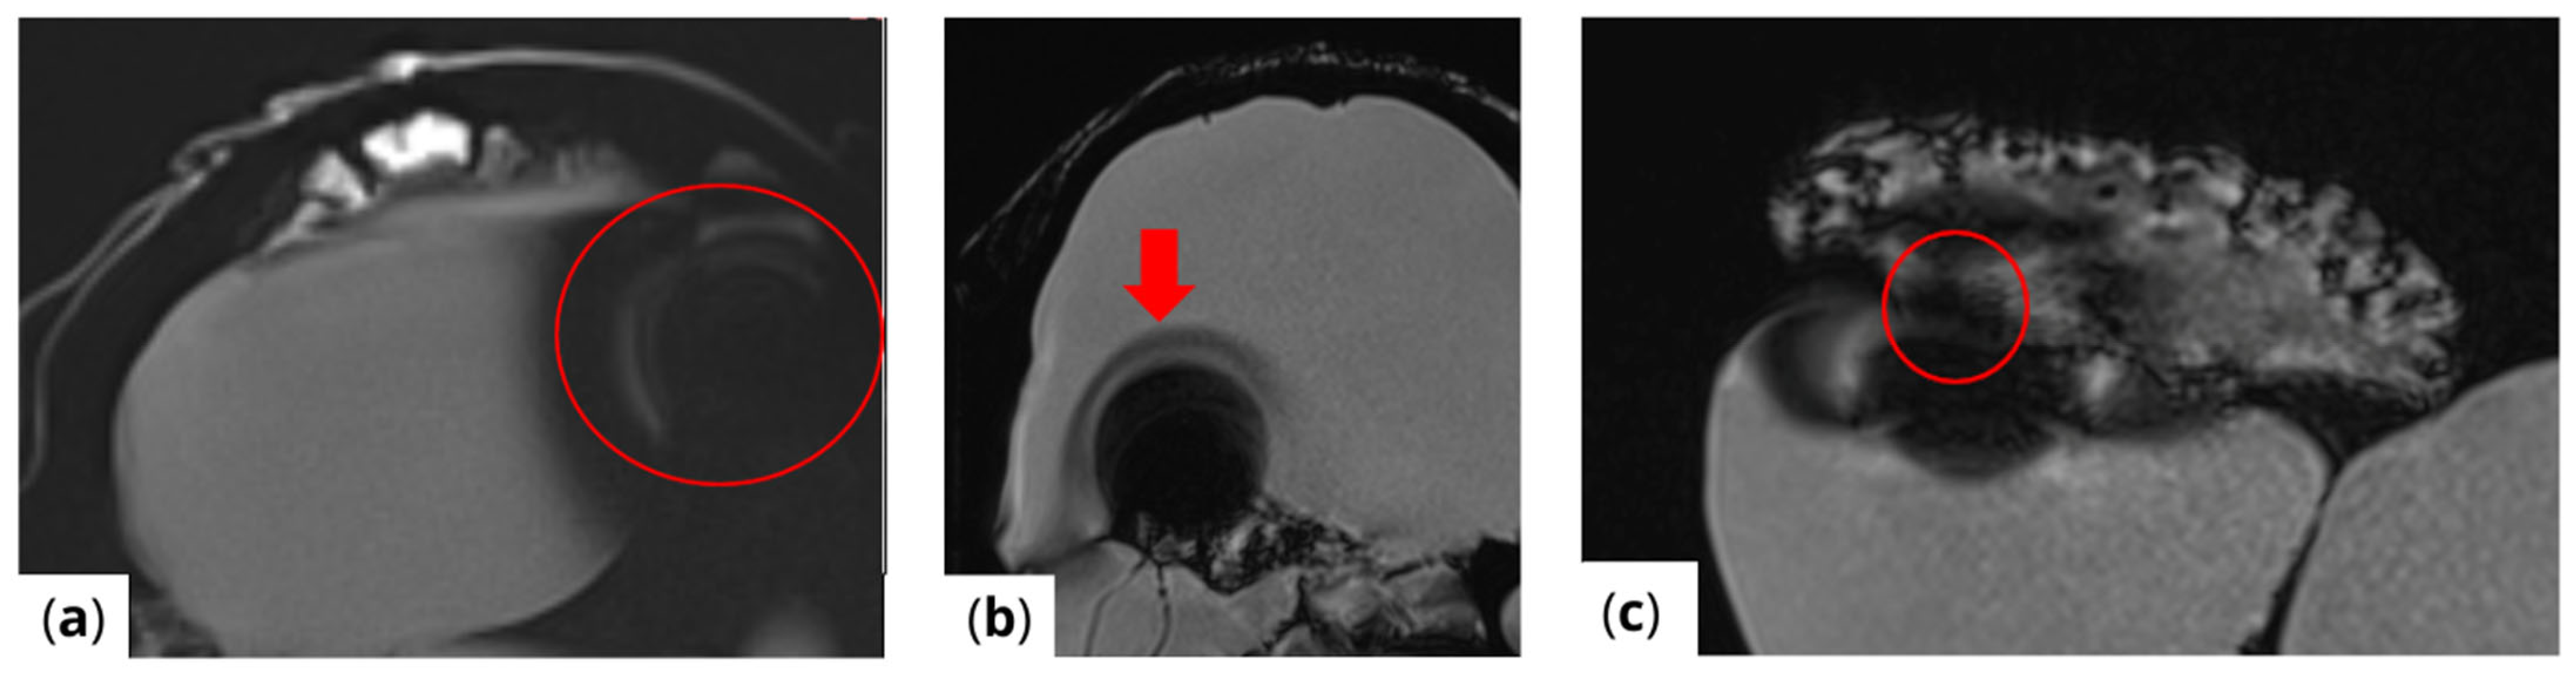

The extent of MRI signal dropout is also influenced by the echo time (TE); a longer TE exacerbates artifact formation at the interface of soft tissues, bone, and air. This effect is evident in images (Figure 3) obtained using t1_starvibe_tra, t1_vibe_fs_tra, and t2_tse_fs_tra.

Figure 3.

Images illustrating the effect of prolonged echo time (TE) on artifact formation at the interfaces of soft tissue, bone, and air (a) t1_starvibe_tra sequence showing signal dropout and distortion near the simulated tumor region, highlighted by the red circle, (b) t1_vibe_fs_tra sequence, with the red arrow indicating residual artifact intensity in the vicinity of the implant interface, and (c) t2_tse_fs_tra sequence, where the red circle marks susceptibility-induced signal loss at the tumor location.